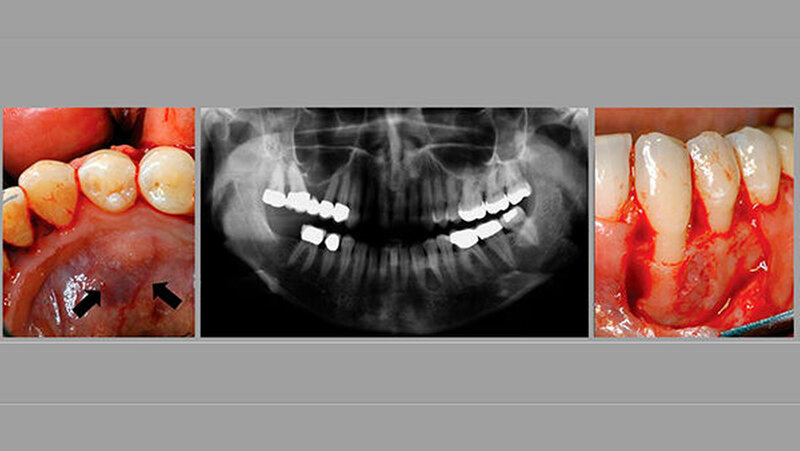

Daraufhin wurde die Patientin im Januar 2006 an die Klinik für Oralchirurgie am Universitätsklinikum Bonn überwiesen. Die intraorale Untersuchung ergibt dort eine kleine Hartgewebeschwellung - eine Knochenexpansion - an der lingualen Seite der Zähne 33 und 34 (Fig. 1A). Weder eine Hypästhesie noch eine Hyperästhesie oder Anästhesie des linken N. alveolaris inferior wurden festgestellt, ebenso wenig Anzeichen von entzündlichen Schwellungen, Eiter oder Einblutungen.

Ein neues Panoramaröntgenbild zeigte eine dreieckige radiopake Läsion zwischen dem unteren linken Eckzahn und dem Prämolaren. Die Basis der Strahlendurchlässigkeit wurde zwischen den divergierenden Scheiteln der benachbarten Wurzeln (Fig. 1B) lokalisiert.

Therapie: erste OP

Zu diesem Zeitpunkt beobachteten die Zahnärzte eine erkennbare weiche Schwellung bukkal der Zähne 33 und 34. Um die Läsion unter örtlicher Betäubung vollständig zu entfernen, wurde von vestibulär eröffnet. Als sie den Mukoperiostlappen freigelegt hatten, sah man, dass die vestibuläre Knochenwand perforiert und darunter eine Läsion vorhanden war (Fig. 1C).